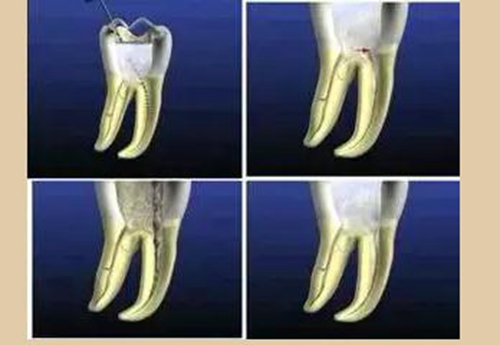

二、根管預(yù)備后形態(tài)

牙體缺損的修復(fù)需要將剩余牙體組織制備成一定形態(tài),以利修復(fù)體的良好固位。根管充填為了致密封閉根管系統(tǒng)也需要良好的根管預(yù)備后形態(tài)。

常規(guī)概念的根管預(yù)備后形態(tài)有: ( 1 )便宜形態(tài)( convenience form )。 ( 2 )保持形態(tài)( retention form )。

( 3 )抵抗形態(tài)( resistance form )。

1. 便宜形態(tài)

便宜形態(tài)是自切端或咬頜面朝向根尖的直線開擴(kuò)尖錐形態(tài),減少污染物推出根尖孔,方便沖洗、根管充填和側(cè)壁施壓。

2. 保持形態(tài)

保持形態(tài)是根尖狹窄部?jī)?nèi) 1 — 2mm 的一段距離,由擴(kuò)大器回轉(zhuǎn)切割而不貼根管壁提拉切割制成,是擴(kuò)大器的原始形態(tài)(近似平行)。在測(cè)試主牙膠尖時(shí)給測(cè)試者有一個(gè)牽引抵抗 (tugback) 的感覺。

3. 抵抗形態(tài)

抵抗形態(tài)是根管預(yù)備的根尖形態(tài),它是由擴(kuò)大器或根管銼尖端 75 度角自然切割而成。其目的是防止根管充填材超出根尖孔,并且使根尖封閉更加嚴(yán)密。